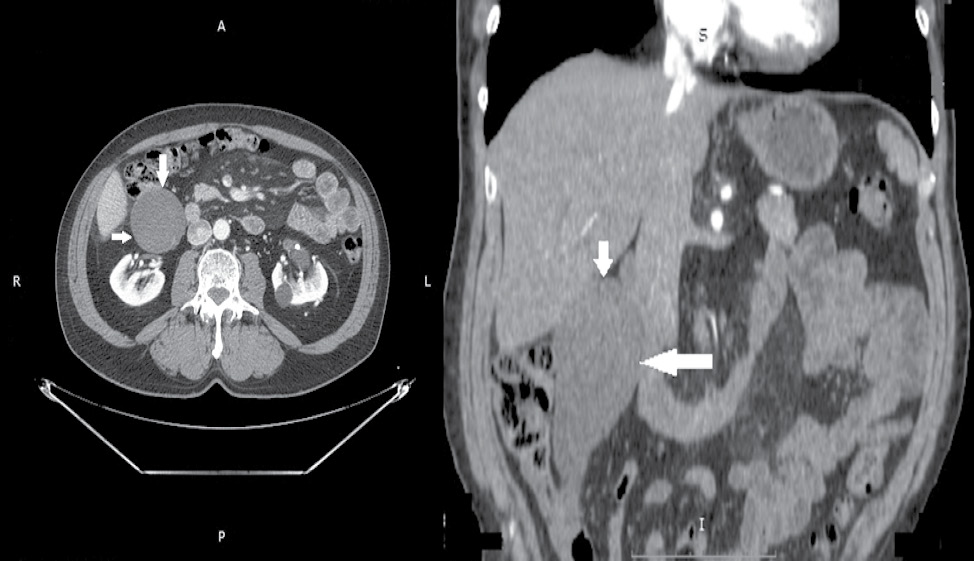

The removed preparation (a cecal appendage with a mucocele) with a size of 14 × 6 × 6 cm was opened, and a cloudy whitish-yellow gelatinous content was found in the lumen (Figs. 2 and 3). A sample was sent for pathohistological examination.

Fig. 2. An intraoperative picture of mucocele of the appendix

Рис. 2. Интраоперационная картина мукоцеле червеобразного отростка